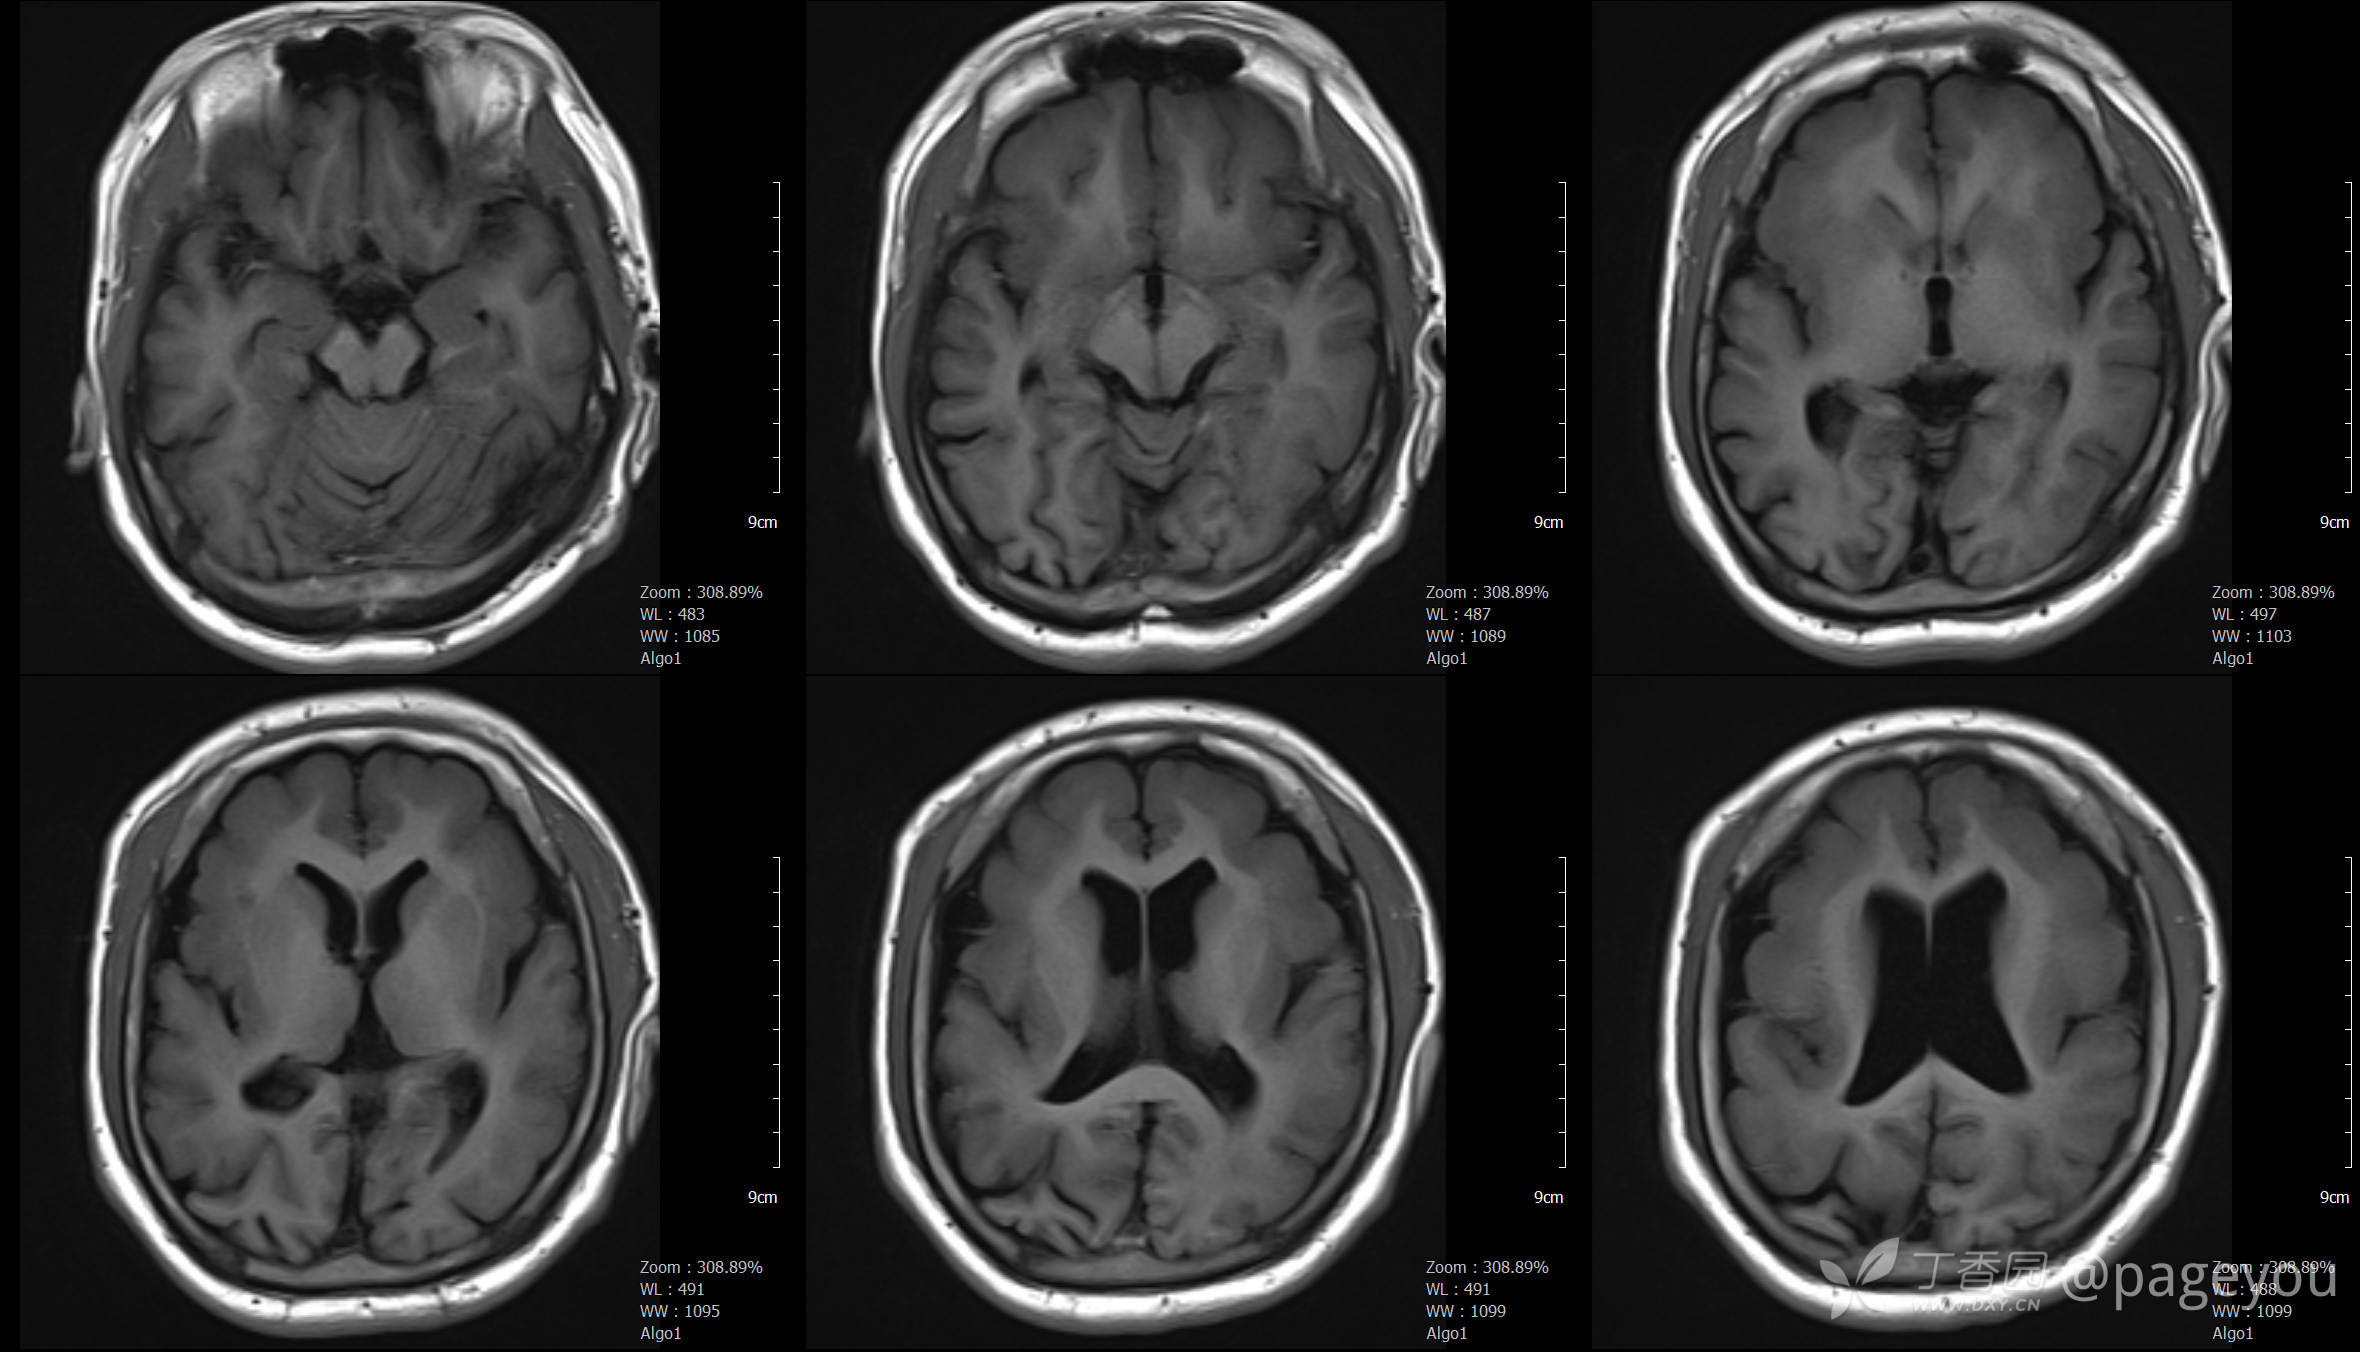

头颅CT:

头颅MRI: